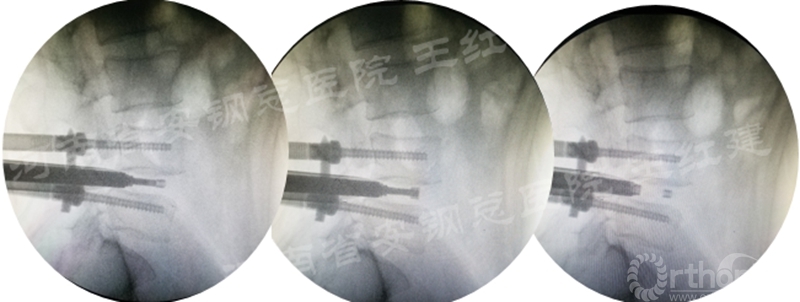

应用通道技术进行植入融合时,首先要更换工作套管,通过枪钳、抓钳的应用处理椎间盘,接着进行自体骨或同种异体骨及cage植入,并通过C臂透视确定试模型号放置融合器,最终完成植骨融合。

确定融合器位置

四、经皮螺钉技术固定

在固定的步骤可以先期进行经皮螺钉置入,再进行融合器的置入,进而实现充分固定。

手术步骤:先期经皮螺钉置入、再进行融合器的置入